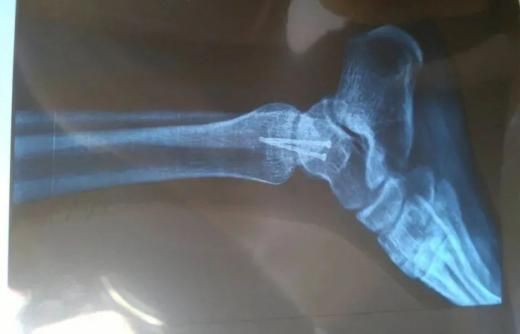

据世界卫生组织统计,每年有将近30万人因为摔倒而死亡,而摔倒引起的受伤情况更是数不胜数,其中老年人占相当大比例。

根据年龄的不同,摔倒造成的伤害也各不相同。老年人因为骨质相对疏松,一旦摔倒极易造成骨折,同时因血压升高引起脑溢血、中风、心脏病等其他附加伤害。